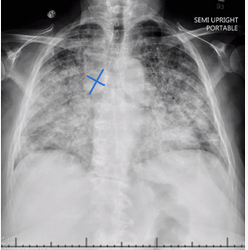

Chest radiograph with bilateral diffuse infiltrates, cardiac enlargement, and extremely enlarged azygos vein (blue markers), signaling venous hypertension typical of cardiogenic pulmonary edema.

The clinical presentation of myocarditis varies widely, with chest pain common early and then a wide range of cardiac functional states, ranging from well-preserved ventricular function to severe cardiogenic shock. Arrhythmias and conduction disturbances are common with more severe ventricular dysfunction. ECG changes in general are nonspecific, with tachycardia and nonspecific ST-T wave changes often present (as in this patient). This patient’s chest radiograph was typical of cardiogenic pulmonary edema, with bilateral diffuse infiltrates, cardiac enlargement, Kerley B lines, and an extremely large azygos vein signaling venous hypertension (see Figure 4, with blue markers showing azygos vein). Echocardiography is useful to determine the degree of ventricular impairment, which was severe in this patient.